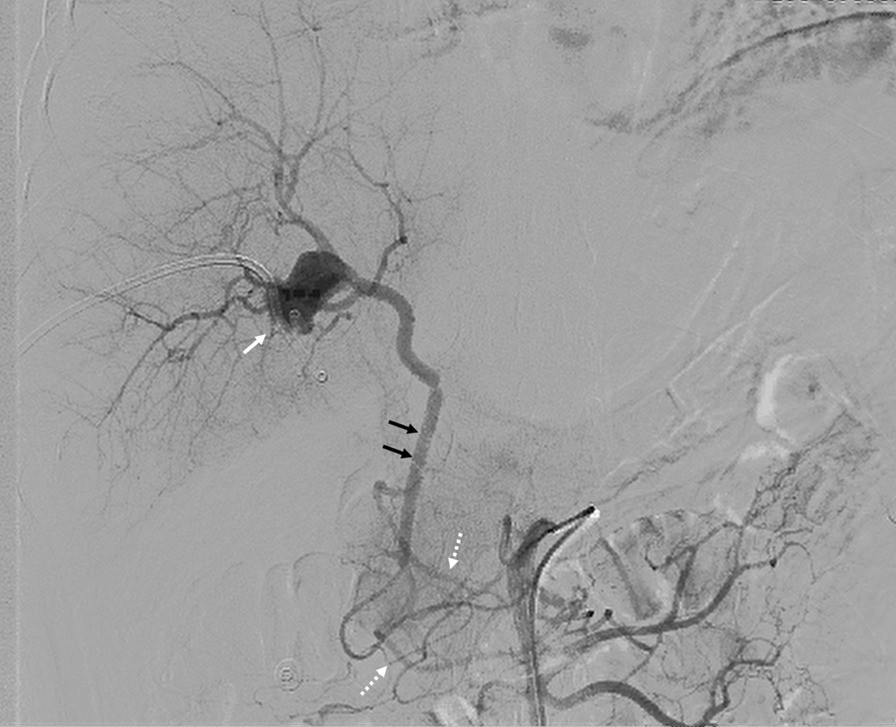

Fig. 3

Superior mesenteric angiogram demonstrating collateral circulation and hepatic artery pseudoaneurysm. Note anterior/posterior pancreaticoduodenal arch (white dotted arrows), gastroduodenal artery (black solid arrows), and pseudoaneurysm (white solid arrows)